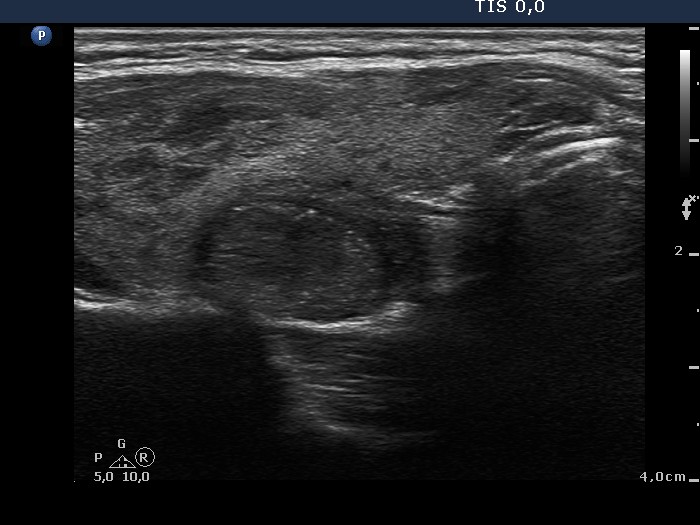

100 consecutive cases of papillary cancer - case 038 (ultrasonographic picture 3)

Right lobe, another longitudinal scan. The lesion presents halo. Note that similar, tiny bright punctate echogenic granules can be found both within and outside the nodule. Note the discontinuation of the caspule and the abutment which exeeds 80%.